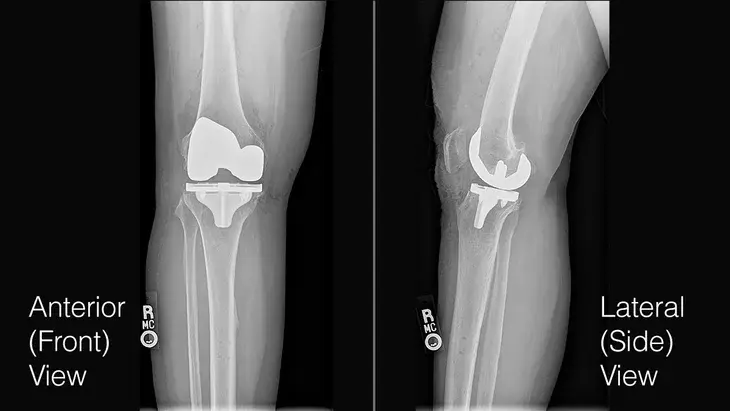

“Those people can have a new form of a knee replacement, which is really a knee resurfacing where we use a robot to precisely remove the arthritic part of the joint and cap it with a metal cap on the end of the femur, and a metal and plastic tray on the tibia,” he said. That robotic precision is so good that cement is not needed, Stone explained. They press fit the new component right onto the bone, and the body will grow into the porous undersurface of the component.